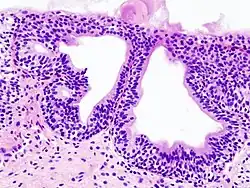

Cystitis glandularis

Cystitis glandularis is the transformation of mucosal cells lining the urinary bladder. They undergo glandular metaplasia, a process in which irritated tissues take on a different form, in this case that of a gland.[1] The main importance is in the findings of test results, in this case histopathology. They must distinguish a benign metaplastic change from the cancerous condition urothelial cell carcinoma.[2] It is a very common finding in bladder biopsies and cystectomies, and most often found in the trigone area. Cystitis glandularis lesions are usually present as small microscopic foci; however, occasionally it can form raised intramucosal or polypoid lesions. The cystitis glandularis lesions are within the submucosa.

There are two main types of cystitis glandularis, non-mucinous and mucinous (intestinal). The difference is in the cellular production of mucin, a normal feature of colonic and intestinal epithelial cells but not of urothelial cells.[3] Another distinction is made between focal areas and diffuse involvement of the bladder. Whereas focal areas are more common, diffuse involvement is seen in chronically irritated bladders, such as in paraplegics or those with bladder stones or indwelling catheters. Individuals with diffuse intestinal-type cystitis glandularis are at increased risk for developing bladder cancer.

Cystitis glandularis arises from and merges with Von Brunn's nests, which are groups of urothelial cells (cells of urinary tract) within the lamina propria and submucosa, formed from budding from the surface mucosa. They are considered normal. Cystitis cystica is a similar lesion to cystitis glandularis, where the central area of the Von Brunn's nests have degenerated, leaving cystic lesions. Other metaplastic entities in the urinary bladder include squamous metaplasia and nephrogenic adenoma.